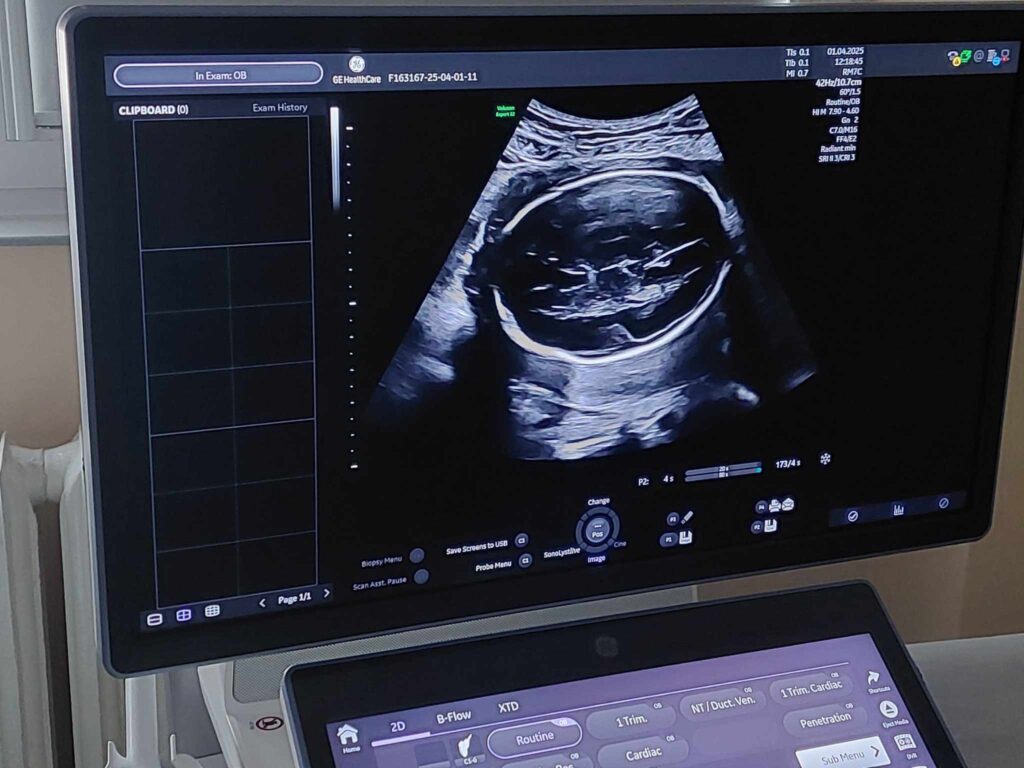

Kobiety w ciąży od 1 kwietnia mogą wykonać badania prenatalne w Klinicznym Szpitalu Wojewódzkim nr 2 w Rzeszowie.

Badanie refunduje NFZ, a pozwala ono na wczesne wykrycie wad płodu i rozpoczęcie leczenia jeszcze w łonie matki

Badanie prenatalne jest bezinwazyjną metodą, aby skorzystać z bezpłatnych badań wystarczy mieć skierowanie od lekarza prowadzącego ciąże. Można umówić się telefonicznie dzwoniąc do poradni położniczo – ginekologicznej szpitala.